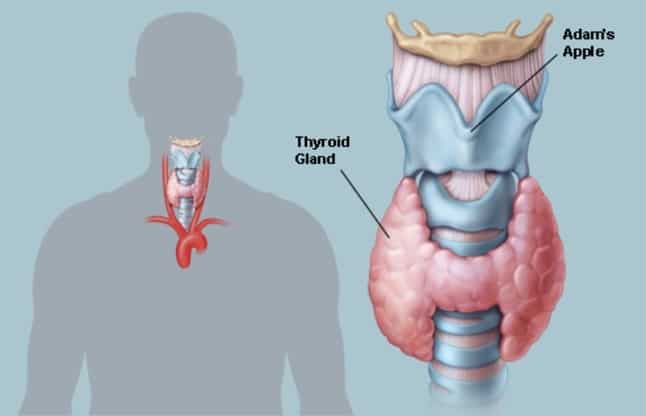

The Thyroid Checkup is extremely beneficial for patients with Hypothyroidism or Hyperthyroidism and Infertility . Thyroid checkup helps to monitor treatment in patients with thyroid diseases. Dr. Debabrata Sarkar<span...